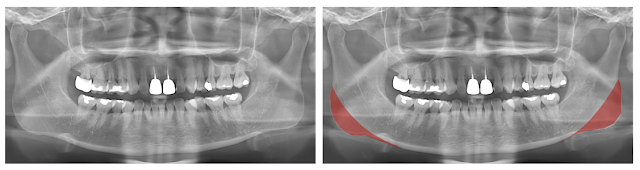

S小姐因為下臉較寬的問題困擾很久,一開始 Botox 治療覺得稍微有改善,但經過一陣子就覺得沒什麼效果。從 X ray可以看到明顯的下顎骨角是造成下臉較寬的原因,經由手術將下顎骨角縮小,不但臉部線條變得柔和,臉頰凹陷的問題也獲得改善。

療程效果因人而異,上圖為該案例實際術後成效